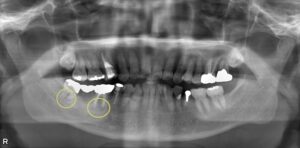

歯根分岐部病変に対する根管治療と外科的処置の併用症例

右上の歯ぐきの腫れを訴えて来院されました。 右上6番はレントゲン写真やCT撮影から、歯の神経および歯根の分岐部位に感染を起こしていることが…